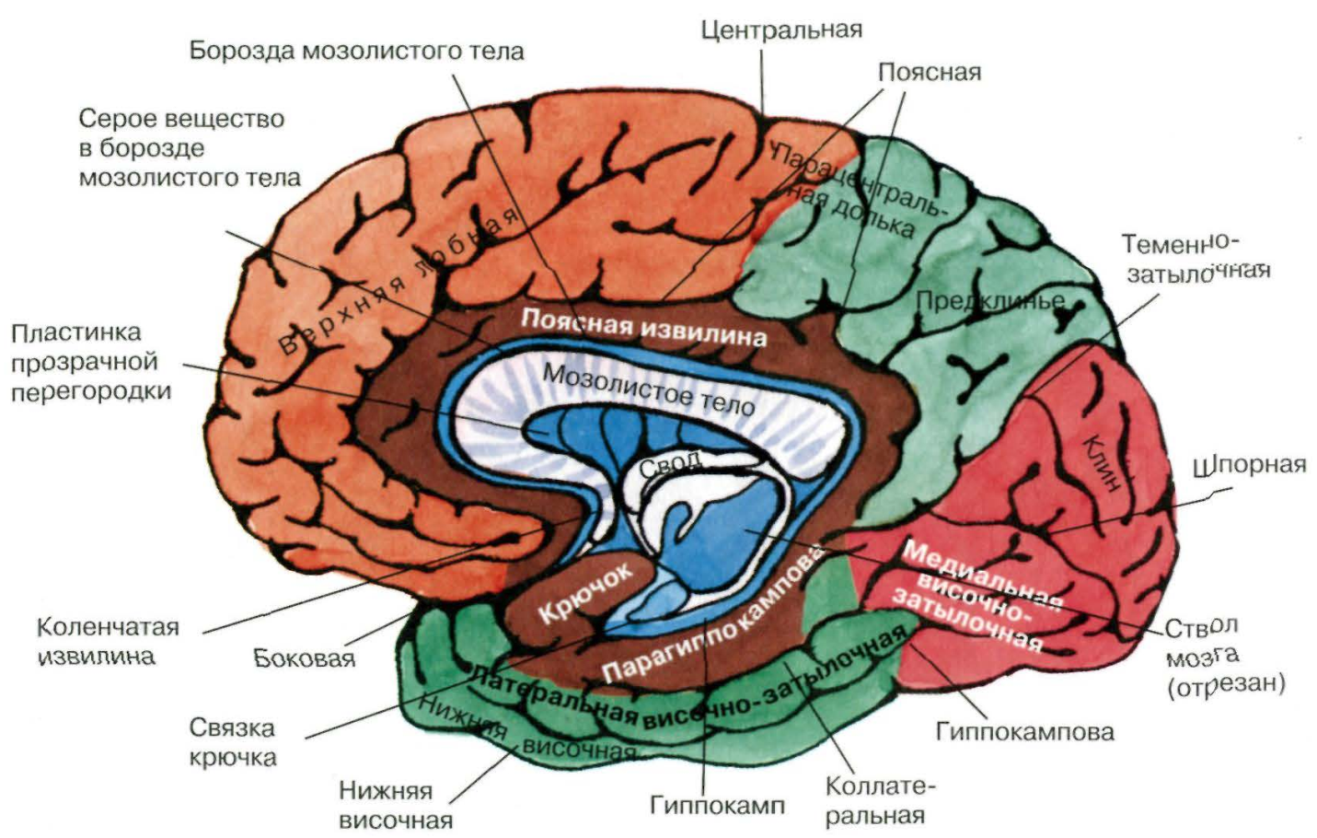

Анатомические снимки верхнелатеральной поверхности головного мозга